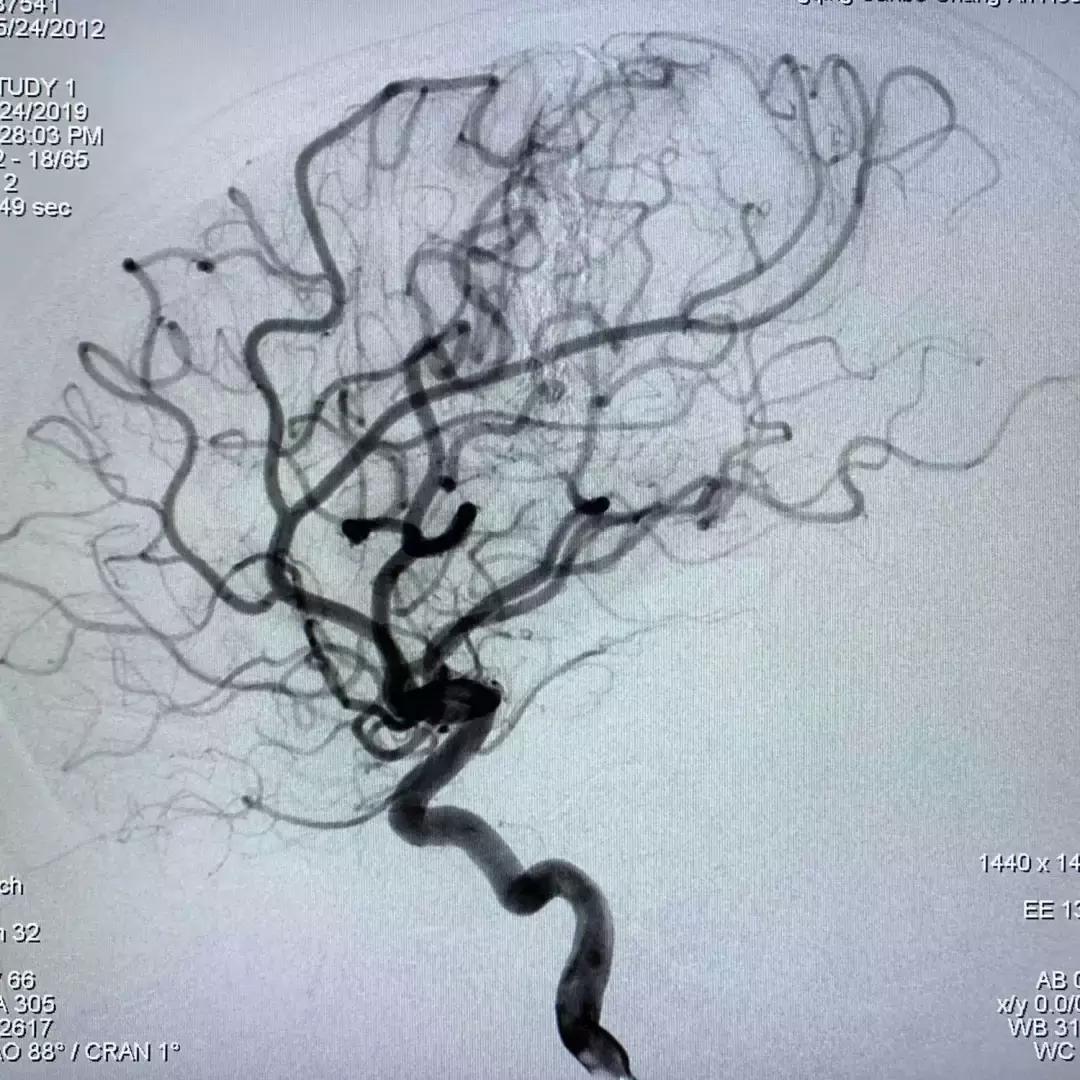

DSA脑血管造影提示脑血管畸形

从造影图上可以看到,畸形不大,但在脑子深部,位于功能区;正位像形似月牙,侧位看很弥散;而且均为终末细支或者细小侧支供血。经过和首都医科大学三博脑科医院刘加春教授远程会诊讨论,决定先给患儿实施栓塞治疗,这样既可以降低再出血概率,又可以尽量避免开颅手术造成的新的脑组织损伤,为小强的功能恢复最大限度创造条件。

刘加春教授反复分析造影。由于畸形的供血动脉真的太细小,而且终末支供血;导管很难超选到位,在超选插管过程中穿破出血的概率较高。最后刘加春教授决定选用最柔软的漂浮微导管来试行寻找合适的栓塞动脉,并不断手推造影了解结构。

如上几图只是刘加春教授寻找合适注胶动脉过程中的一部分

术中,刘加春教授通过这样的尝试锁定了两支动脉。如何注胶呢?由于血管结构原因,胶浓度不合适常常弥散不好,达不到畸形团“铸型”栓塞的效果。最后,刘加春教授决定采用稀释6倍的Glubran胶进行栓塞。